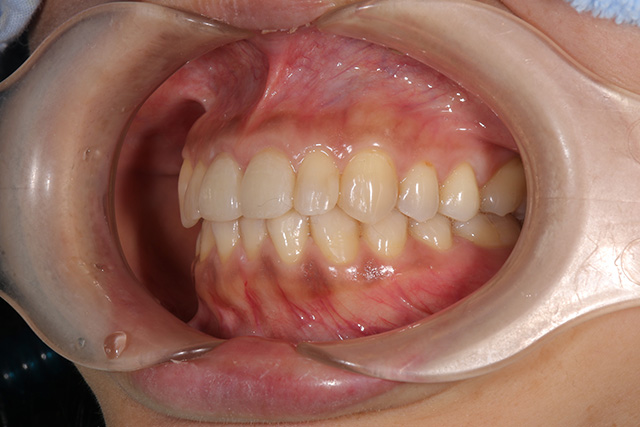

審美症例